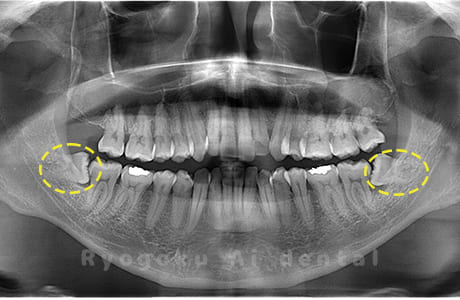

Case01

-

- 原因

- 水平埋伏智歯

- 治療内容

- 下顎の水平埋伏智歯を抜歯

<リスク・副作用>

手術後は痛み、腫れ、痺れなどの副作用が生じる場合があります。